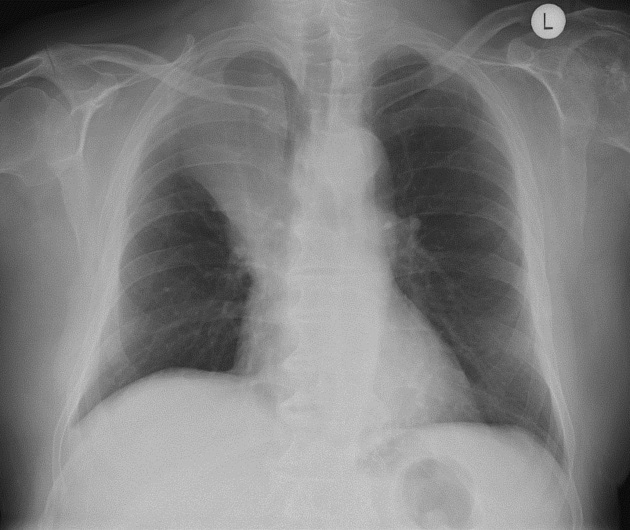

Describe the abnormality demonstrated.

Enlarged heart, Kerley B lines at both lung bases, left-sided pleural effusion, subtle cephalisation - all in keeping with congestive heart failure